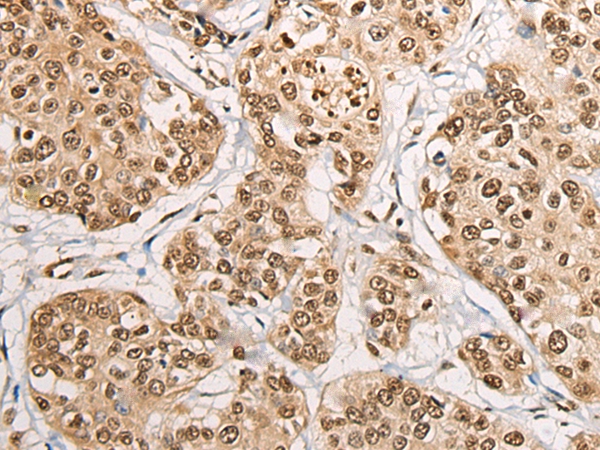

The image on the left is immunohistochemistry of paraffin-embedded Human prostate cancer tissue using 46640(PHF21A Antibody) at dilution 1/50, on the right is treated with fusion protein. (Original magnification: x200)

The image on the left is immunohistochemistry of paraffin-embedded Human esophagus cancer tissue using 46640(PHF21A Antibody) at dilution 1/50, on the right is treated with fusion protein. (Original magnification: x200)